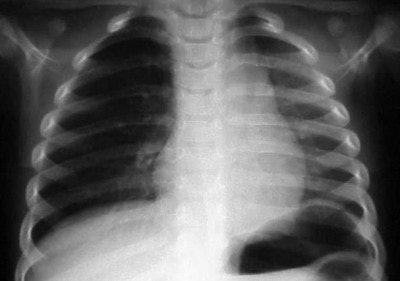

In figure 8, the radiographic technique has been adjusted to show lung markings after the placement of a chest tube on the left. The chest tube, however, appears to be abutting the ETT, and notice the air shadow extending around the pericardium and along the diaphragm, consistent with the diagnoses of pneumomediastinum.